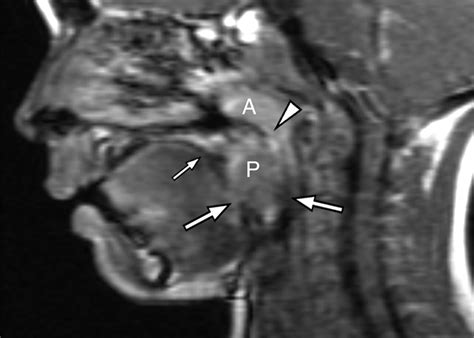

• Adenoids: These are located high up in the throat, behind the nose and the roof of the mouth (the soft palate). Because of this hidden location, they cannot be seen by looking directly into the mouth; a doctor requires a special mirror or a small, flexible camera to visualize them.

To understand the body’s immune defense system, one must look at Waldeyer’s ring, a collection of lymphoid tissue that forms a circle at the back of the throat. Within this circle, we find the pharyngeal tonsils (commonly known as the adenoids) and the palatine tonsils (commonly known simply as the tonsils). While it is technically accurate to say that both structures are types of tonsillar tissue, they are not identical.

• Palatine Tonsils: These are the two oval-shaped lumps of tissue you can easily see when you ask a child to open their mouth wide and say “ah.” They sit on either side of the back of the throat.

A specialist will likely perform a physical examination and may use an endoscope to view the nasal passage. In some cases, a sleep study might be ordered if there is concern regarding pediatric sleep apnea. By gaining a clear understanding of the location and severity of the enlargement, parents can work with their medical team to develop an effective, personalized treatment plan.